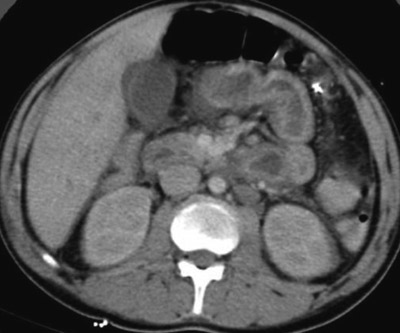

Nøytropen enterokolitt er en alvorlig tilstand, med en mortalitet på 8–40 % (2, 6, 7). Den kan progrediere raskt fra milde magesmerter og subfebrilia til livstruende septisk sjokk. Klinisk undersøkelse er av begrenset verdi og må suppleres med CT-undersøkelse (fig 1) eller ultralyd abdomen, som gir best diagnostisk resultat og utelukker andre patologiske tilstander (2–4).

Lang aplasitid ble påvist hos dem som trengte kirurgisk behandling. Kortvarig aplasi begrenser inflammasjonen til tarmmucosa (mukositt), langvarig aplasi forårsaker kontinuerlig bakteriell invasjon av tarmveggen, med ulcerasjoner (fig 2), nekrose og perforasjon. Disse funnene er i samsvar med observasjoner gjort av Wade & Nava (8). Imidlertid forekommer økt fortykkelse av tarmveggen også ved kolitt utløst av Clostridium difficile, transplantat-mot-vert-sykdom, cytomegalovirusinfeksjon og tarmiskemi (4). Derfor må disse tilstandene utelukkes hvis radiologiske funn skal ligge til grunn for diagnosen nøytropen enterokolitt.